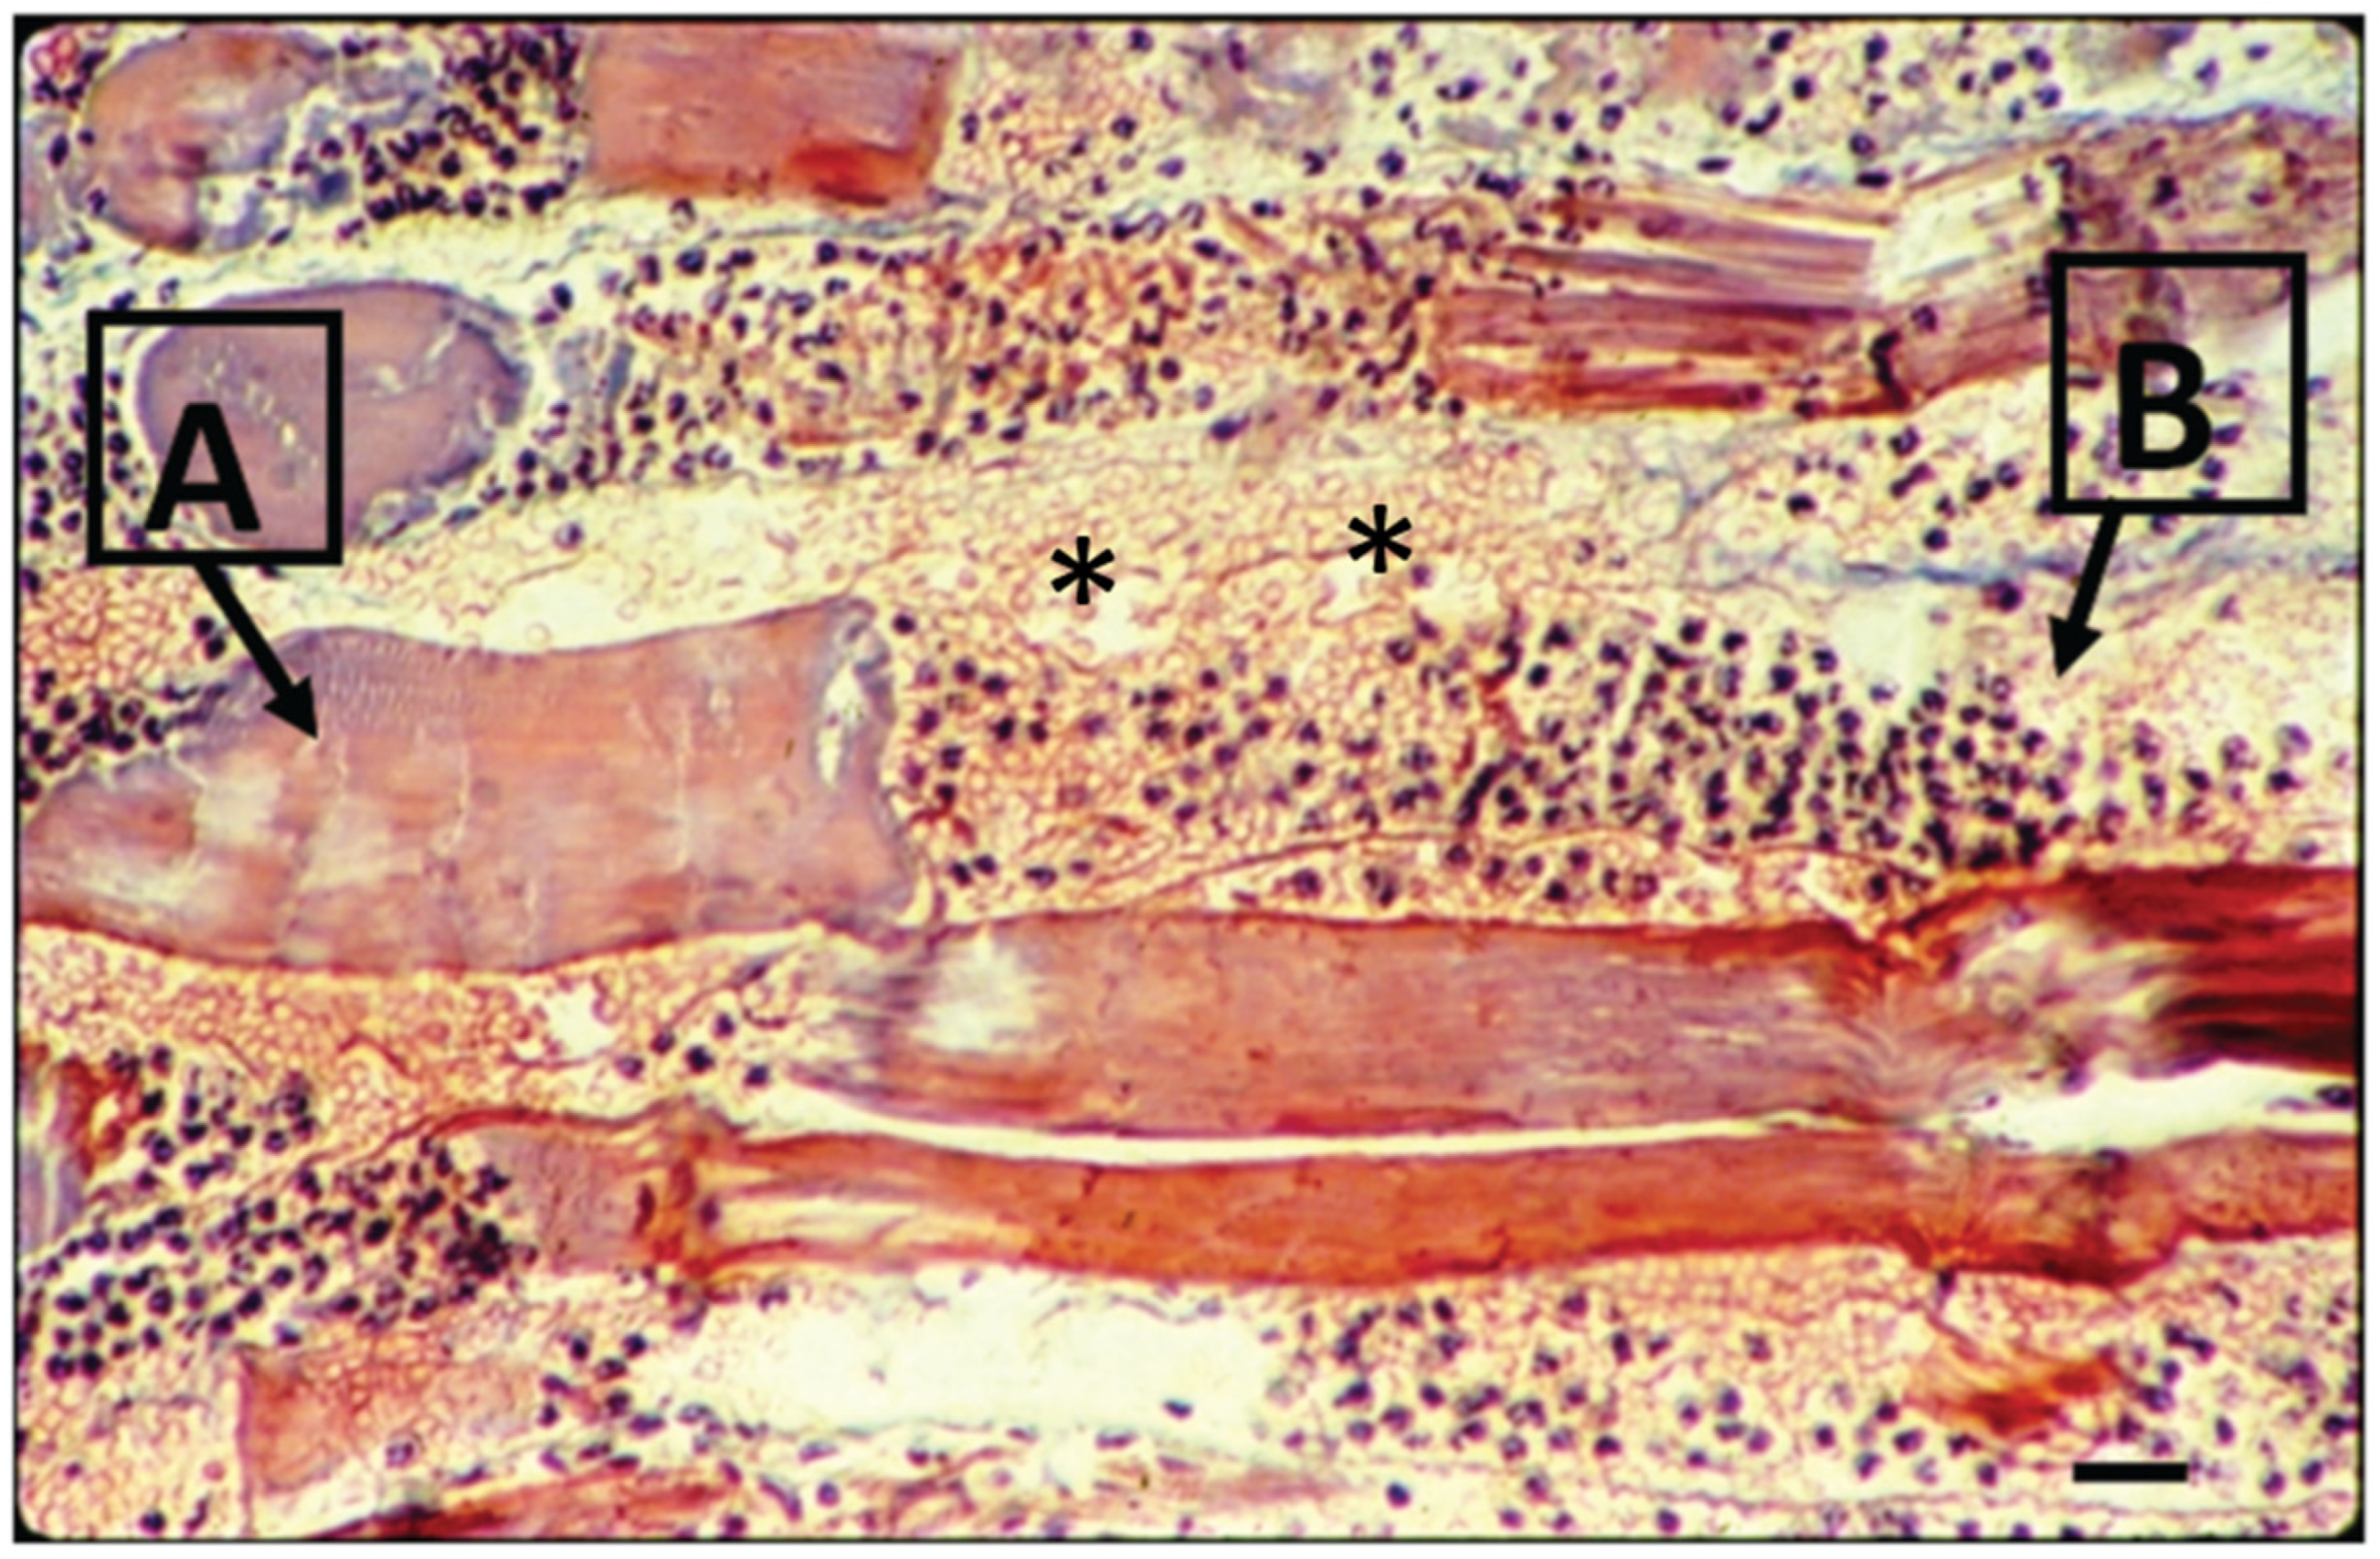

4. Tissue Hemorrhage and Damage Induced by Bothrops Snake Venoms

5. Snake Venom Metalloproteinases